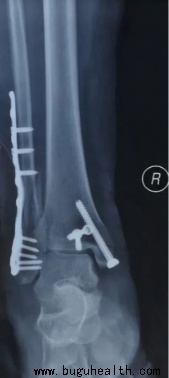

对于Ⅲ级踝关节扭伤及保守治疗无效者可以考虑手术治疗,具体方法有直接缝合、带线锚钉修复、伸肌支持带加强修复、肌腱移植重建等,对于骨折错位患者,也可以选择手术治疗。

很多急性踝关节扭伤患者,认为没有大碍,照样下地行走,没有及时治疗,导致损伤加重,甚至骨折错位。临床上很多患者,尤其是老人,扭伤后未及时就医,到最终行走困难,彻夜疼痛时才来就诊;有的患者拍片检查时才发现骨折错位或关节脱位,错过了治疗的最佳时期,最终留下踝关节疼痛、慢性关节炎、踝关节不稳、骨折不愈合等后遗症,严重影响生活质量。布骨医疗专注于运动医学与肌骨康复。对于脊柱侧弯筛查与矫正(脊柱侧弯支具定制),骨科术前术后康复,运动康复,肌骨疼痛(颈肩腰腿痛),足踝康复(矫形鞋垫定制)都有很好治疗方案。